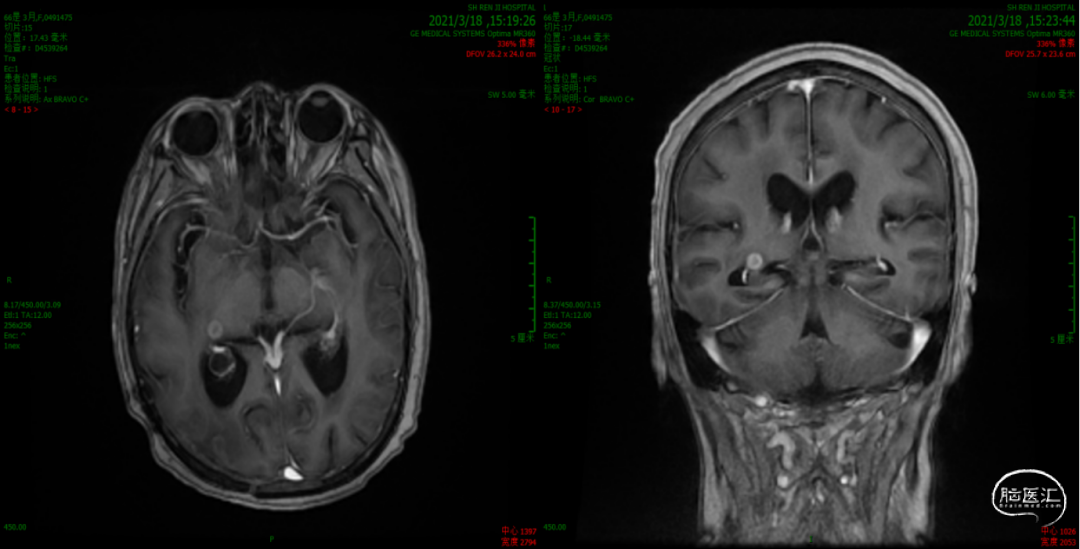

3. 2021年3月18日,2021年3月起,患者诉左侧肢体乏力,需搀扶行走。影像学检查显示,右侧脑室后角旁见结节样环形强化灶,直径7-8mm。MRS:NAA峰可见下降,Cho峰升高。Cho/Cr为0.748,Cho/NAA为2.13,考虑肿瘤复发可能。患者行射波刀治疗(24Gy/4FX),TMZ+安罗替尼2周期,TTFields重新定位,电场治疗调整贴片位置。